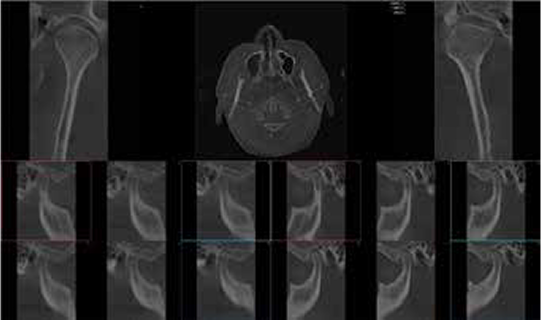

Symmetry view provides a cross-sectional image of the temporomandibular joint area for bilateral TMJ diagnosis